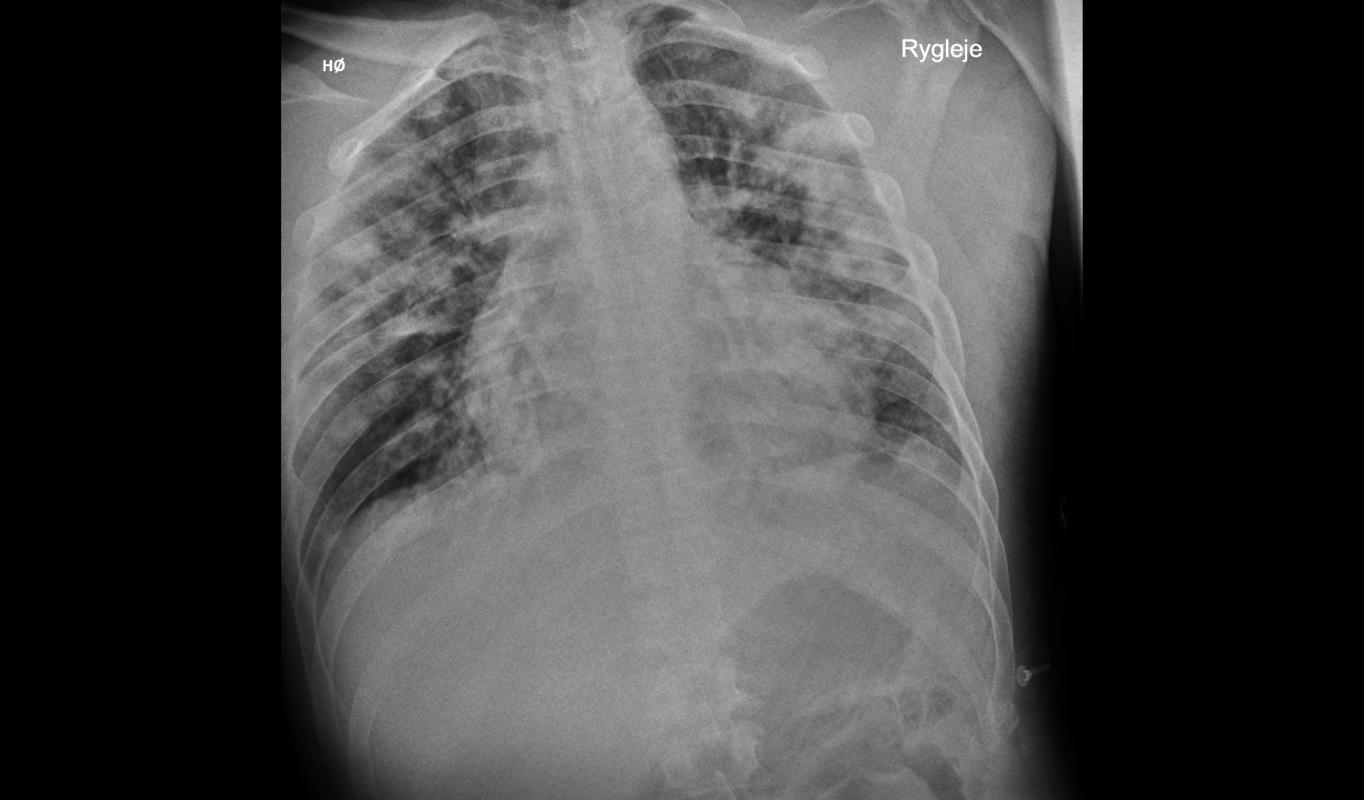

6e48014ee809241c64d7de5a12b7b8e3.jpg

初次胸部 X 光检查显示双侧弥漫性肺泡浸润病变,提示肺炎。